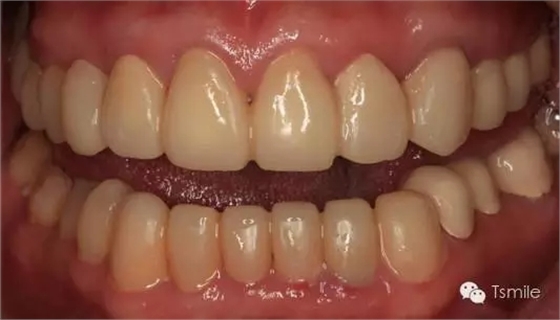

圖6:最終修復(fù)體完成 來(lái)源于tsmlie

前兩個(gè)美學(xué)分析和美學(xué)表達(dá)過(guò)程已經(jīng)確定了患者滿意的最終的美學(xué)修復(fù)設(shè)計(jì),也就是已經(jīng)確定了最終修復(fù)體的形態(tài)、大小、排列、牙齦曲線等各種美學(xué)參數(shù),美學(xué)實(shí)現(xiàn)就是復(fù)制前面已經(jīng)確定的美學(xué)設(shè)計(jì)的過(guò)程,包括牙體預(yù)備、印模制取、修復(fù)體制作、修復(fù)體試戴粘接等過(guò)程。

例如面對(duì)一個(gè)牙列重度磨耗的美學(xué)修復(fù)患者,我們首先根據(jù)患者主訴和美學(xué)檢查形成美學(xué)設(shè)計(jì),然后通過(guò)數(shù)碼圖像表達(dá)美學(xué)設(shè)計(jì)思想,制作診斷蠟型,口內(nèi)制作診斷飾面,更加真實(shí)地表達(dá)美學(xué)設(shè)計(jì)。根據(jù)患者的要求和口內(nèi)試戴情況調(diào)改診斷飾面,最終確定美學(xué)修復(fù)設(shè)計(jì),即最終修復(fù)體的各種美學(xué)參數(shù)。接下來(lái)就是美學(xué)實(shí)現(xiàn)過(guò)程,在診斷飾面上進(jìn)行精確地牙體預(yù)備,制取印模和工作模型,技師按照最終診斷飾面的形態(tài)、大小和排列制作最終美學(xué)修復(fù)體,最后完成修復(fù)體粘接。